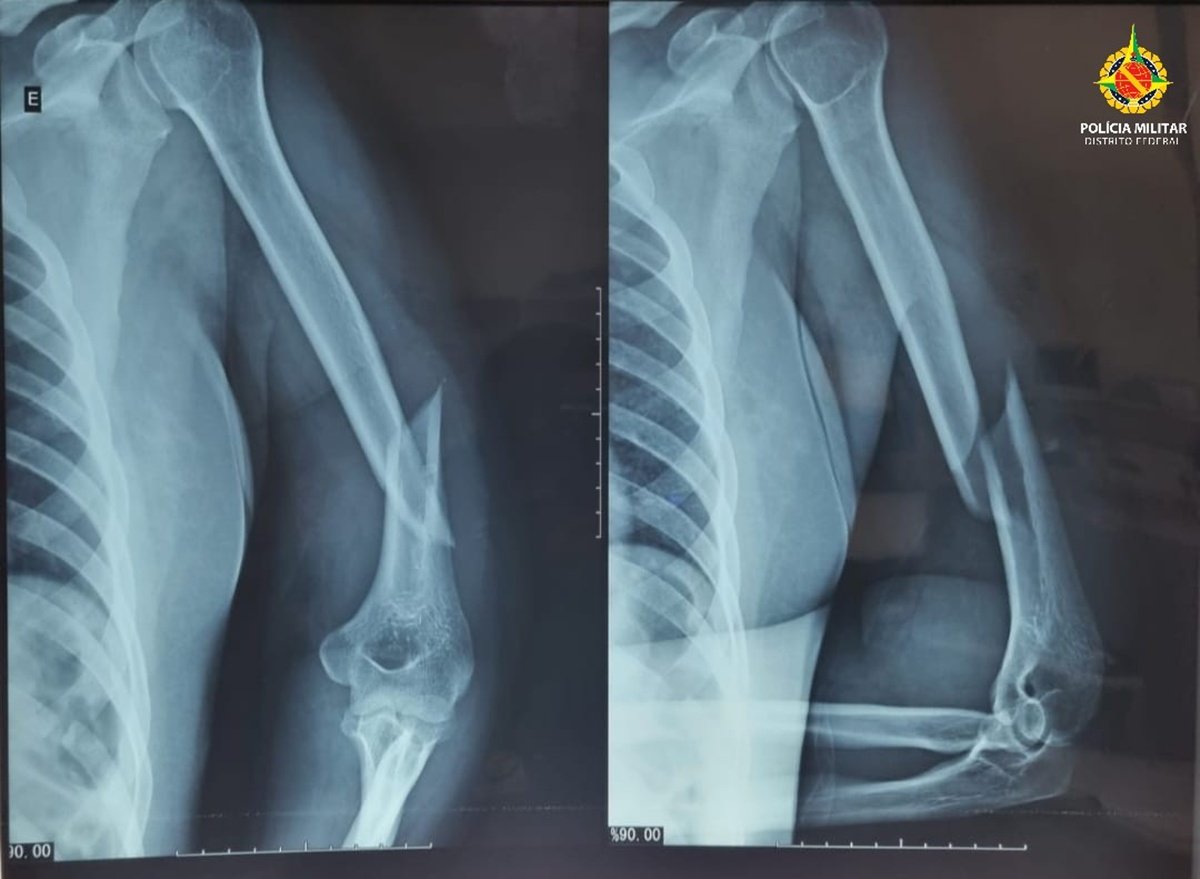

Segundo a Polícia Militar do DF (PMDF), uma equipe foi acionada para atender uma ocorrência de violência doméstica e, no local, constatou que a vítima, de 41 anos, apresentava hematomas no rosto, inchaço ao redor dos olhos, sangramento pelos ouvidos, fratura no úmero esquerdo e luxação no ombro esquerdo.